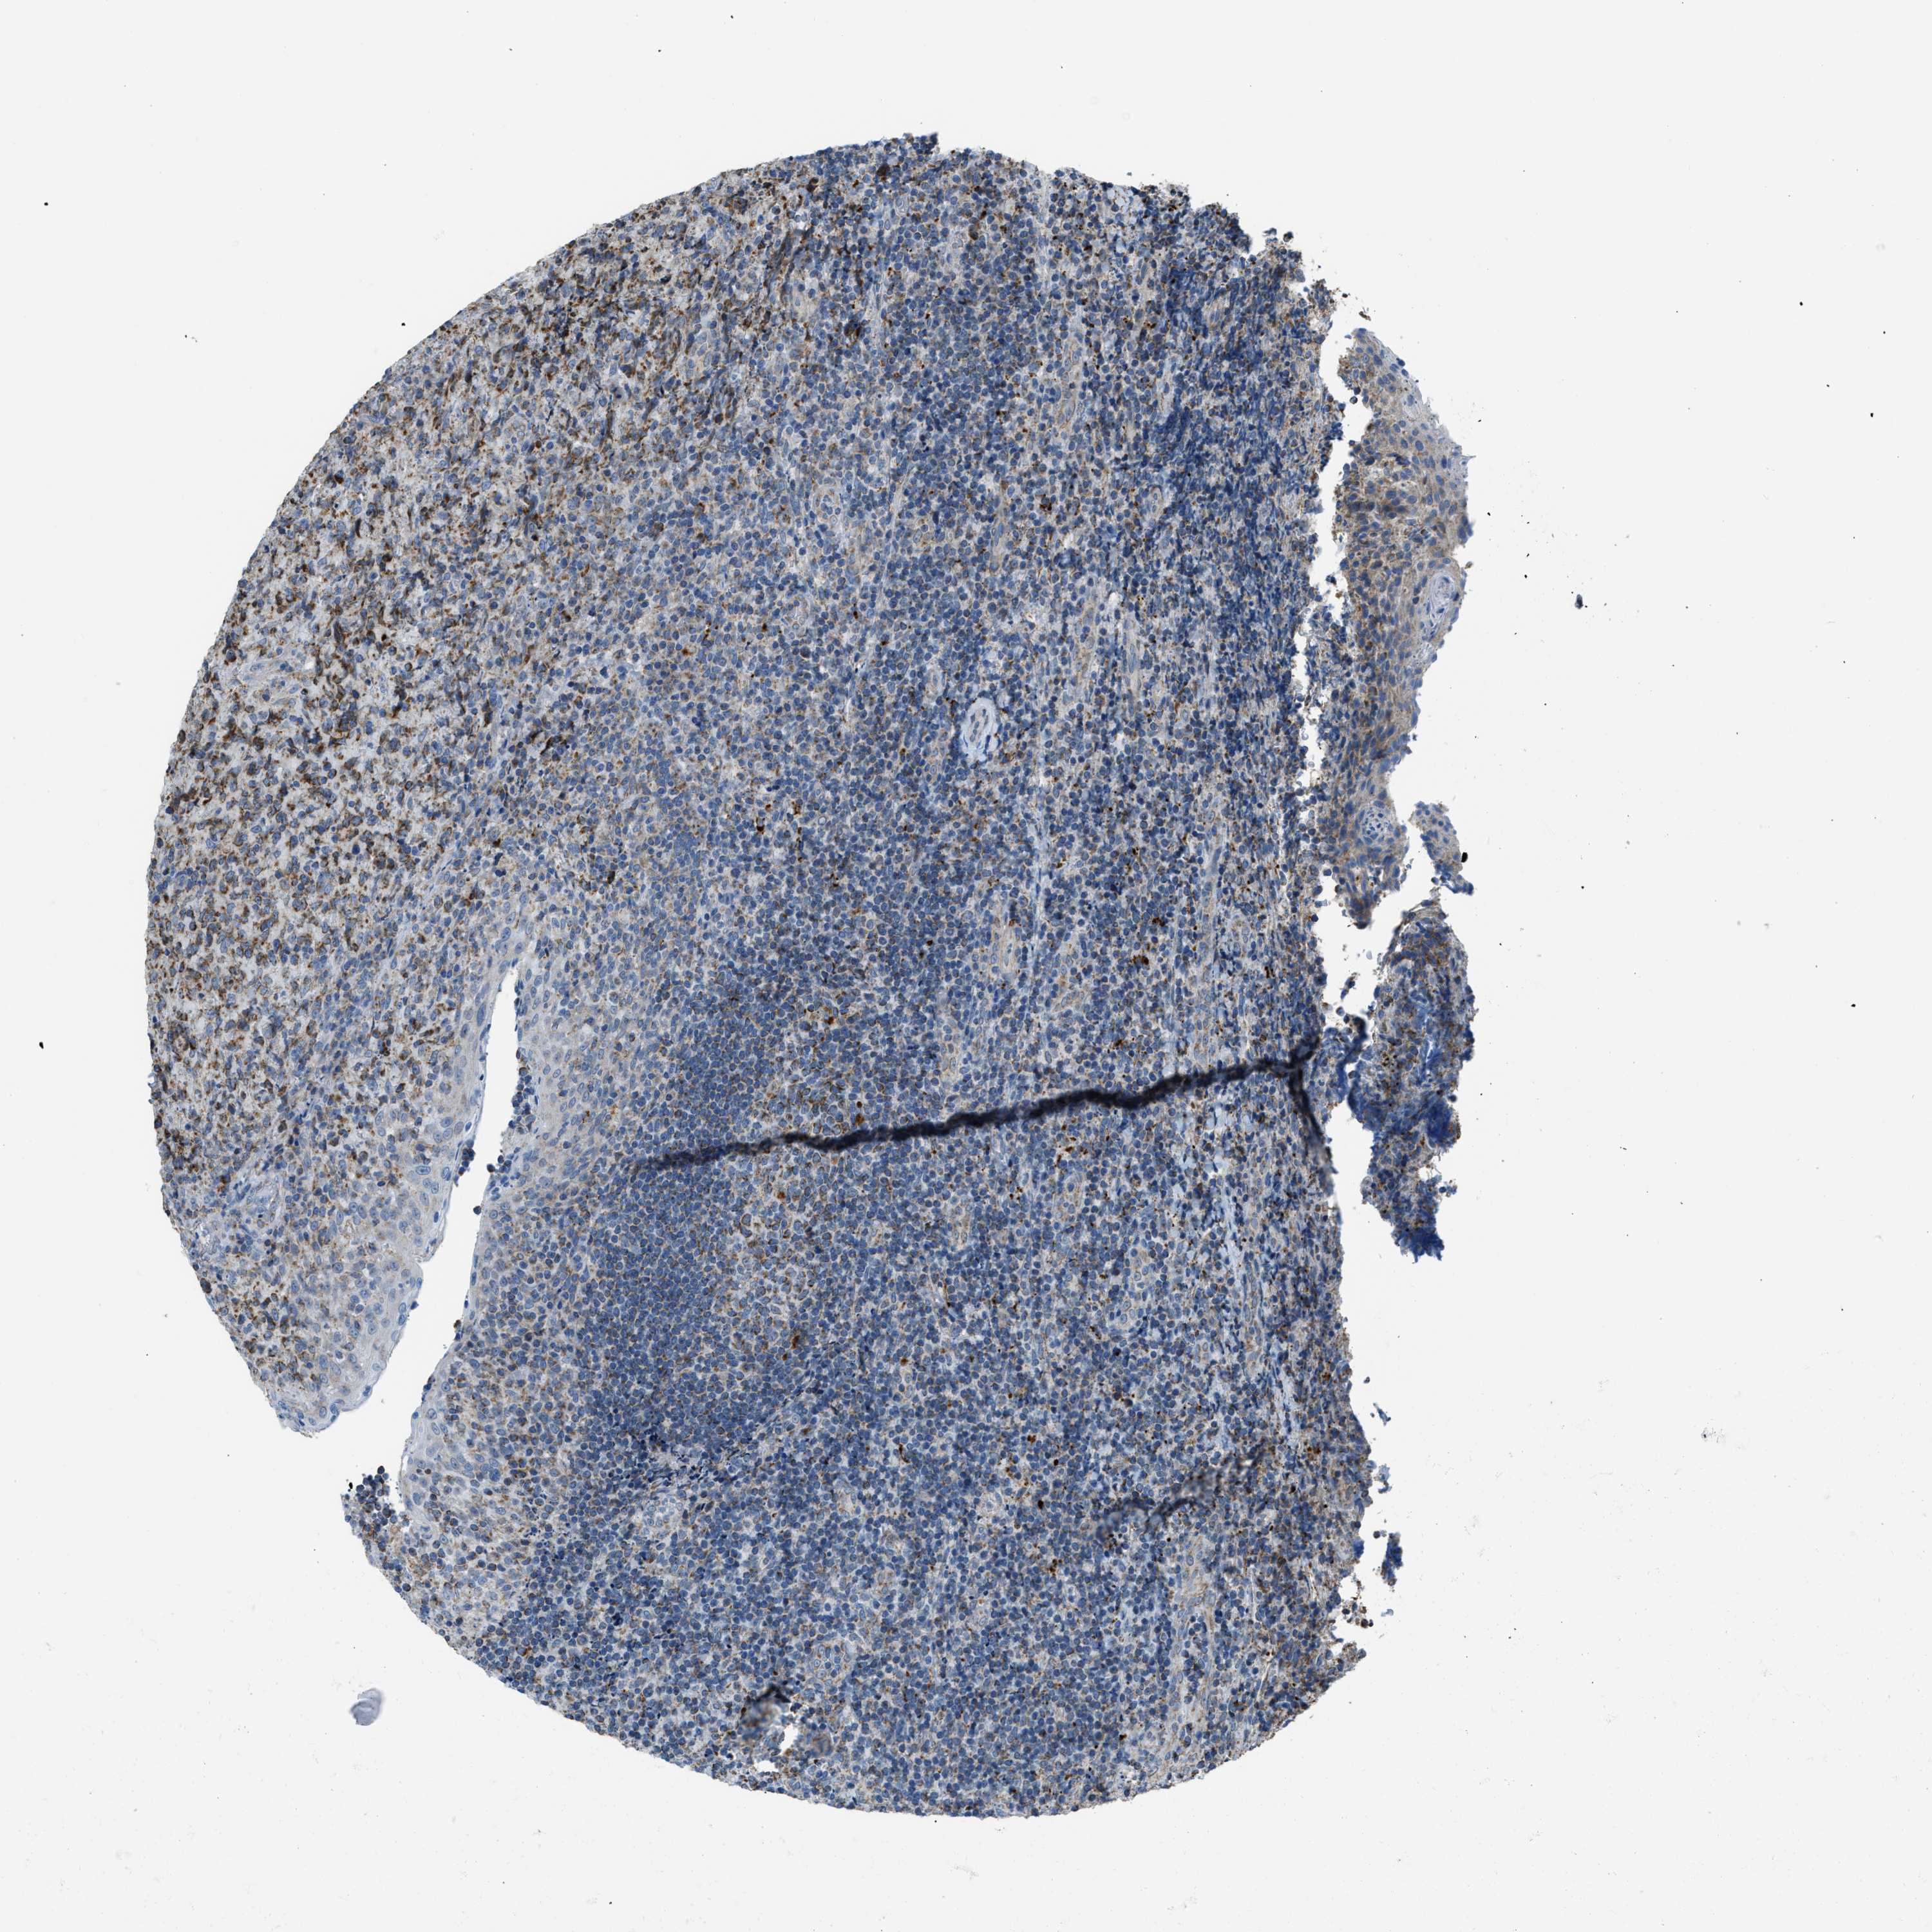

CANCER LYMPHOMA Show tissue menu

LYMPHOMA - Protein expressioni

A mouse-over function shows sample information and annotation data. Click on an image to view it in a full screen mode. Samples can be filtered based on level of antibody staining by selecting one or several of the following categories: high, medium, low and not detected. The assay and annotation is described here.

Each image is clickable and will lead to virtual microscopy that enables deeper exploration of all samples and also displays staining intensity scores, fraction scores and subcellular localization as well as patient and tissue information for each sample.

Antibody HPA016552

Staining

High

Medium

Low

Not detected

Intensity

Strong

Moderate

Weak

Negative

Quantity

>75%

75%-25%

<25%

None

Location

Nuclear

Cytoplasmic/membranous

Cytoplasmic/membranous,nuclear

Hodgkin's disease, NOS

Malignant lymphoma, non-Hodgkin's type, High grade

Malignant lymphoma, non-Hodgkin's type, Low grade